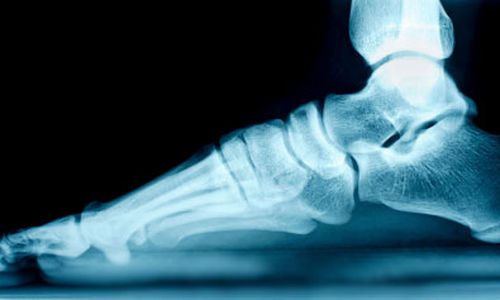

ان الاقدام المسطحة المكتسبة لدى البالغين هي الأكثر شيوعا في النساء فوق سن 40 عاما ، ونتيجة لهذا "تمتد" تدريجيا للوتر الذي يكون بالقرب من عظم الكاحل على مر الزمن ، والمعروفة باسم الوتر الظنبوبي الخلفي. وهذا يسبب بانخفاض قوس القدم للاسفل، مما يسبب الألم.

وجد العلماء أدلة على زيادة نشاط بعض الأنزيمات الحالّة للبروتين في عينات أوتار القدم. قد تسبب هذه الانزيمات في تحلل مكونات الوتر الظنبوبي الخلفي مما يؤدي إلى ضعف الأوتار ، مما يسبب في نقصان تقوس القدم.